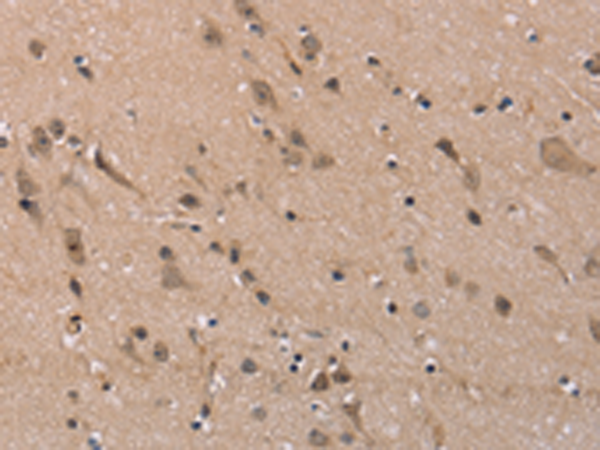

分类: 科研抗体货号: P08315别名: MLC-B; MRLC2应用: WB,IHC反应种属: Human, Mouse, Rat